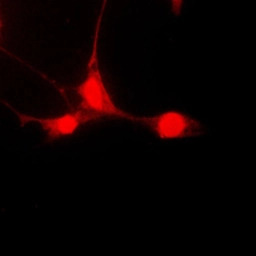

ICC/IF analysis of formalin-fixed HepG2 cells using GTX32268 STAT5A (phospho Ser780) antibody.

Red : Primary antibody

Blue : DAPI

Permeabilization : 0.1% Triton X-100 in TBS for 5-10 minutes